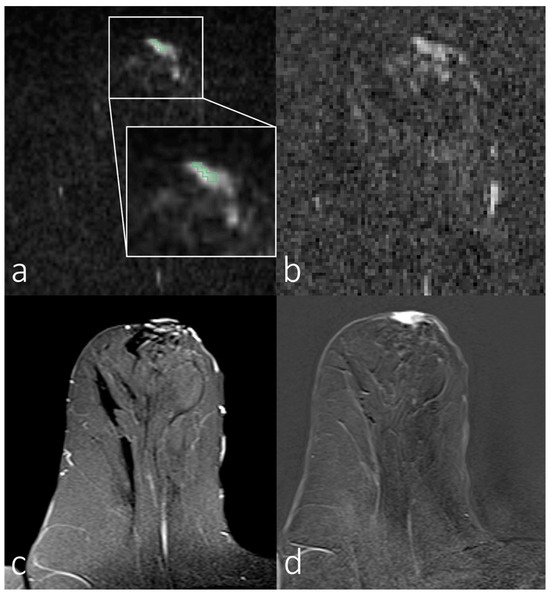

3.2. Analyses of First-Order Statistics Using the ADC

3.3. Evaluation of SNR in the Skin for Assessing ADCs in Skin Pathologies